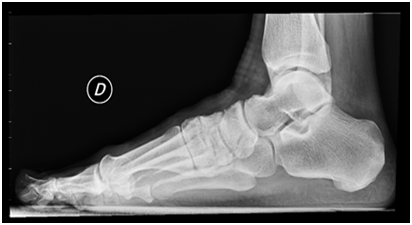

Figure 2 Preoperative Rx showing Hallux Valgus.